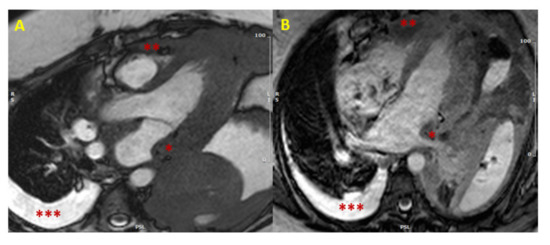

In case of hypertrophy of the interventricular septum at echocardiography, some features may be considered as red flags: among these are a concomitant thickening of the right ventricle, of the atrial walls or of the interatrial septum, and pericardial and/or pleural effusion, because they imply a higher probability of malignancy, and make the diagnosis of a common HCM less likely (Figure 1). Representative of this is the case reported by Kuchynka et al. of a 38-year-old male, with a month-long history of abdominal lymphadenopathy, whose echocardiographic imaging at workup gave grounds for suspicion of HCM [20]. Upon renewed ultrasound investigation, the thickening of the interventricular septum was confirmed, but also a thickening of the right ventricle’s free wall and of the interatrial septum, with a large pericardial effusion, became evident. The ensuing CMR showed diffuse heterogenous late gadolinium enhancement (LGE) in the thickened segments of the myocardium, highly suggestive of a lymphoproliferative disease. Eventually, histological analysis of an enlarged lymph node confirmed the diagnosis of non-Hodgkin lymphoma. After chemotherapy, complete remission was achieved, with normalization of ventricular wall thickness and resorption of the pericardial effusion.

Figure 1. Cardiac lymphoma at CMR. SSFP images in long axis (3-chamber view in Panel (A), and 4-chamber view in Panel (B)) showing concomitant hypertrophy of left atrial wall (single asterisk *) and RV (two asterisks **). The presence of multiple areas of hypertrophy and pleural effusion (three asterisks ***) are “red flags” for malignancy. (CMR = cardiac magnetic resonance; SSFP = steady-state free precession; LV = left ventricle; RV = right ventricle).